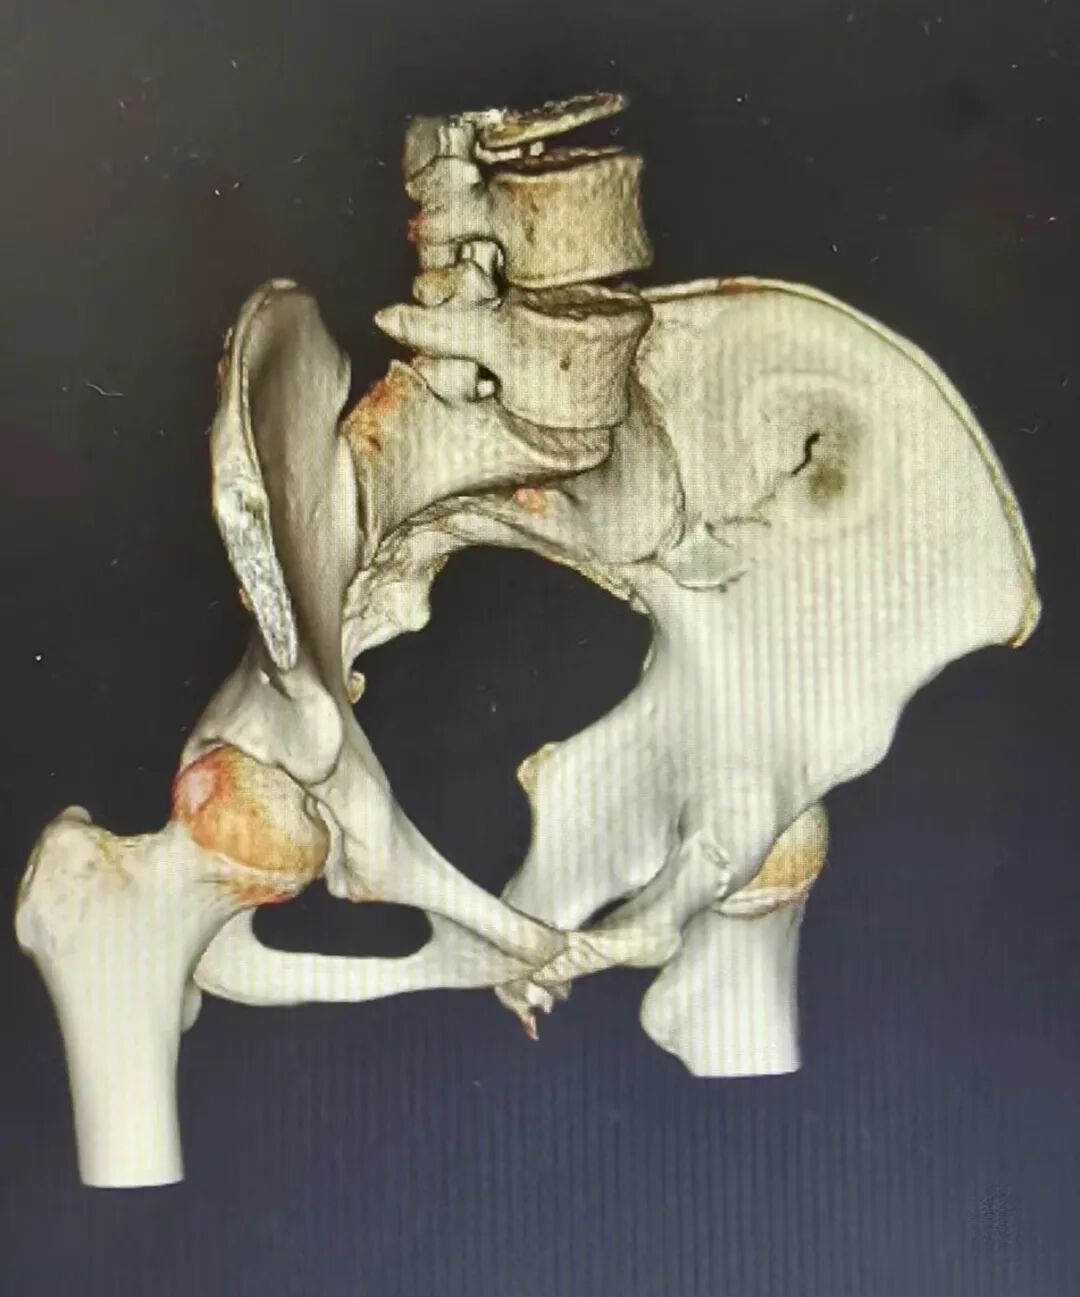

术前

术后

骨盆骨折被称为“创伤骨科的珠穆朗玛峰”,尤其对于高龄患者,手术风险高、术后恢复难度大。骨科三病区接诊的一位90岁老年患者,因意外导致骨盆骨折,传统开放手术创伤大、出血多,对患者身体耐受度要求极高。团队经过详细评估与多学科会诊,决定采用骨盆骨折闭合复位微创LC2螺钉技术,在C臂机精准引导下,通过微小切口完成螺钉植入与骨折复位,全程出血少、创伤小,最大程度减少了对老年患者身体的干扰。术后在医护团队的精细化护理与康复指导下,患者迅速恢复肢体功能,顺利出院,成为安顺市目前年龄最大的骨盆手术成功案例。